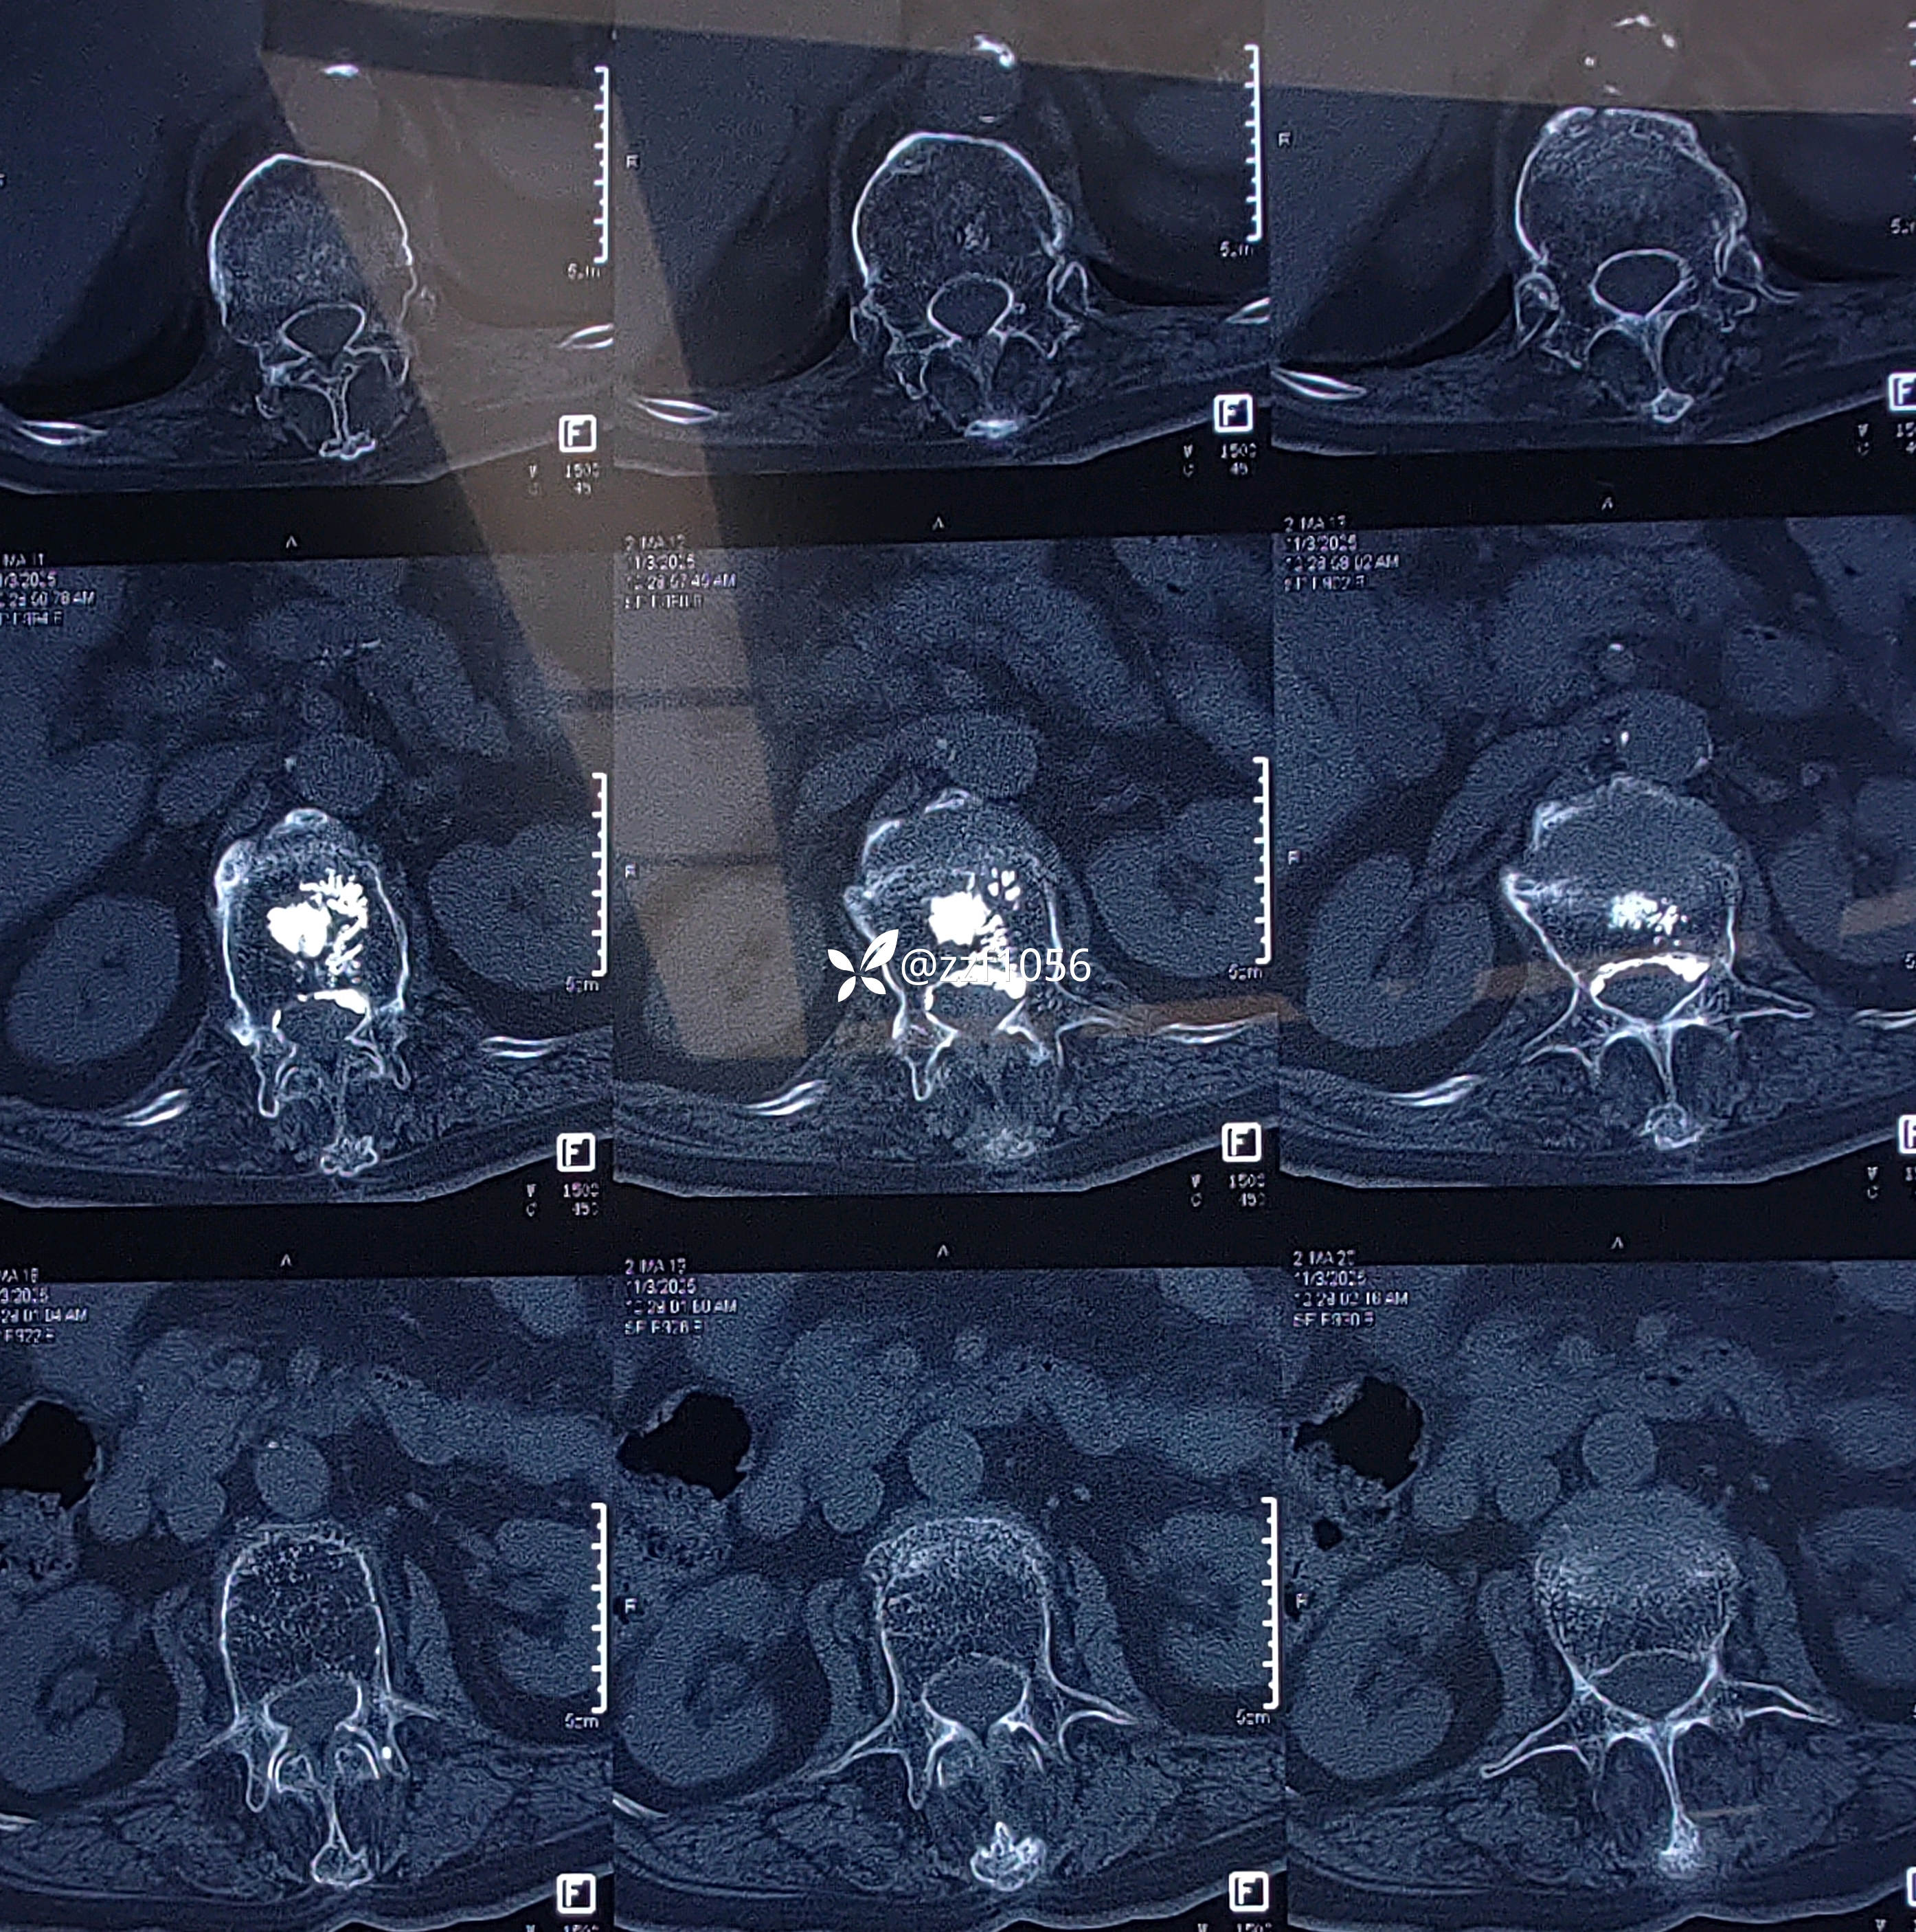

收住院进一步ct检查

果不其然,骨水泥渗漏入椎管内,非常能感受到当时主刀惊出一身汗😓,万幸的是患者并没有神经症状。

家属自诉一年前患者腰1压缩骨折,在外省地医院行椎体成形术,术后恢复良好,日常正常行走。